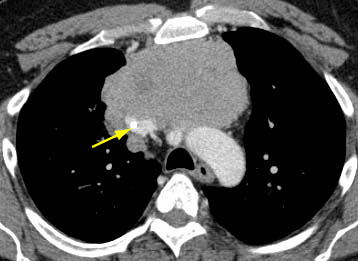

Tomografia computadorizada (TC) do tórax mostrando timoma com encarceramento e invasão da veia cava superior

Do acervo de Cameron Wright, MD; usado com permissão